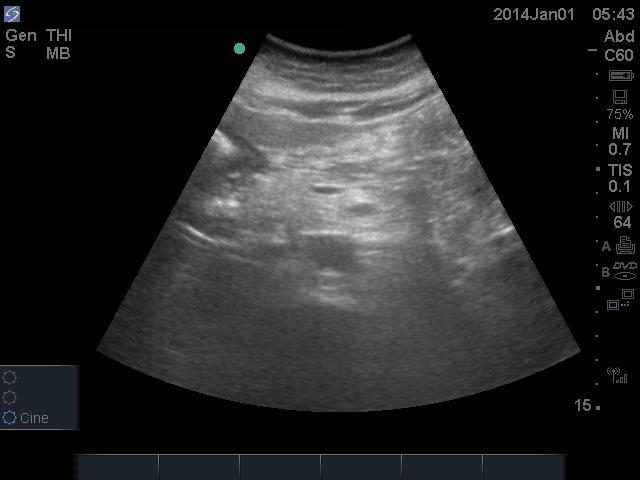

Pericardial U/S showing no PCE found here:

Abdominal U/S showing no AAA found here:

All U/S images are courtesy of McMaster PoCUS Subspecialty Training Program.